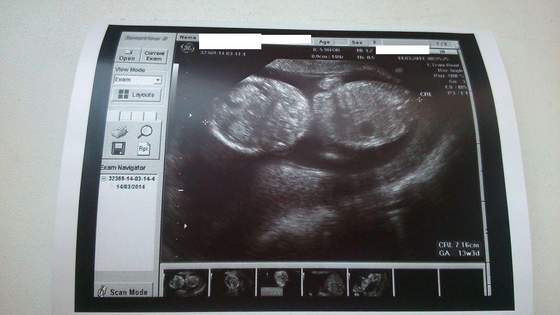

Spytałam też czy z maluchem wszystko ok, to on do mnie że nie mogę pytać czy z małym wszystko ok bo dziecko jest jeszcze maleńskie (ma 7,16 cm) i nie można tego teraz stwierdzić

A to nasz maluszek, jest zdjęcie od plecków